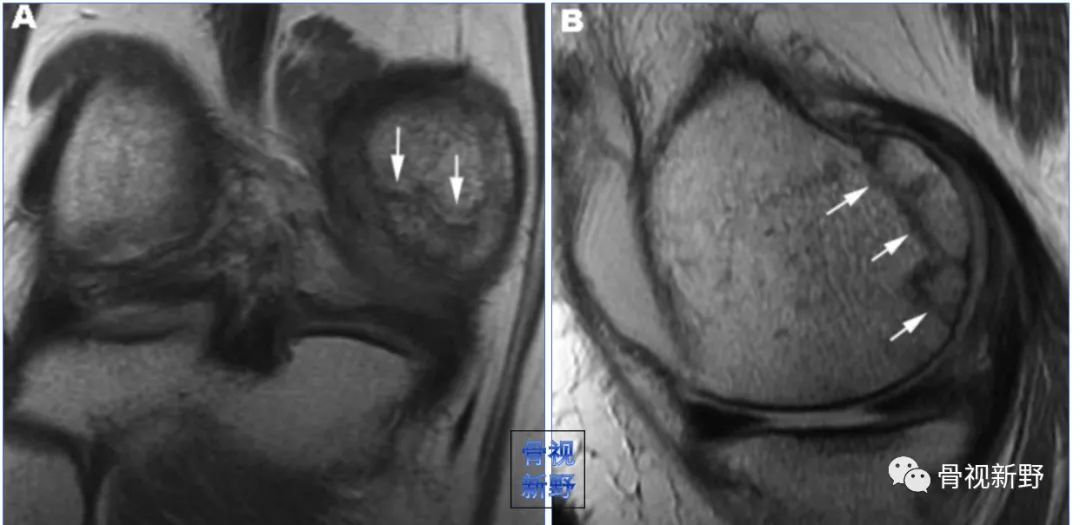

MRI不但可发现隐匿性骨折,还可发现合并的软组织损伤